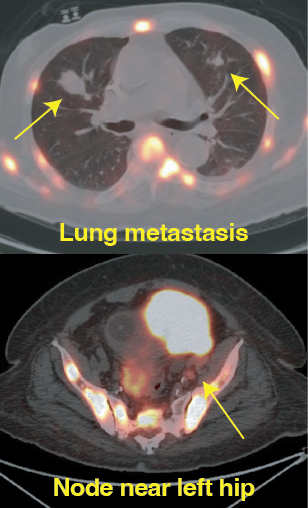

Cancer widely spread to lungs, bones, and lymph nodes

Precision imaging using advanced modalities such as PSMA PET-CT

Accurate identification of disease spread

Resolution of lung metastases

No active lymph node involvement